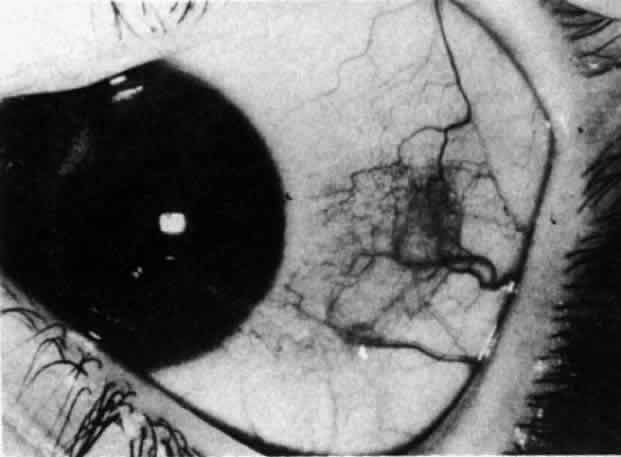

Nodular Anterior Scleritis Although patients with nodular anterior scleritis resemble those with nodular episcleritis on cursory examination, detailed examination reveals marked differences. The nodule or nodules (they may be multiple) consist of scleral tissue that is immovable episclera is tightly adherent to the nodule, which is tender to the touch. Although the sclera sometimes becomes transparent below the nodule, it does not become necrotic, nor does the condition extend beyond the site of the nodule, as occurs in necrotizing scleral disease (Fig. 36). (see Fig. 28; Figs. 34 and 35). The edematous

In contrast to simple episcleritis, the infiltration and edema of nodular episcleritis are localized to one part of the globe, forming a nodule and some surrounding congestion (Color Plate 1B). The nodule can be moved over the underlying sclera, which is not edematous. The scleral plexus of vessels can be distinguished deep to the nodule, lying flat on the sclera and slightly congested but otherwise normal in color and configuration (Figs. 15 and 16). Episcleral nodules may be single or multiple but do not undergo necrosis (see Fig. 16). After multiple attacks of nodular episcleritis in the same location, the superficial lamellae of the sclera show some alteration and become slightly more transparent in this one area. TREATMENT Even without therapy, simple episcleritis improves considerably within the first week and resolves within 3 weeks (Fig. 17). Provided the eye is not too uncomfortable, most patients can be persuaded to leave the eye untreated, because the condition will resolve spontaneously. However, if it is believed that some treatment is desirable, topical corticosteroids or locally applied nonsteroidal anti-inflammatory drugs (NSAIDs) may make the eye more comfortable and speed resolution slightly (see Fig. 17).9 Use of corticosteroid drops must be continued for several days after the inflammation has subsided to prevent the exacerbation of the condition that occurs if they are stopped suddenly. Prednisolone, betamethasone, or dexamethasone drops may be administered hourly until redness disappears, and then three times daily for 4 to 5 days. Under no circumstances should topical steroids be administered continually for more than a few weeks at a time because of the very real danger of inducing steroid glaucoma and cataract. If the condition fails to respond immediately, other treatment regimens should be sought. Ocular NSAIDs can be administered four times daily until redness disappears. Glaucoma and cataract have not been observed after prolonged use, but many patients become intolerant to the use of the ointment or complain of stinging and irritation. Whereas simple episcleritis resolves rapidly without therapy, the resolution of nodular episcleritis is much slower. Local therapy is consequently of much more value; the same regimen of treatment is followed. In the few patients in whom episcleritis becomes indolent, or in whom recurrences are so numerous that the patient becomes incapacitated, it is reasonable to consider systemic therapy with NSAIDs such as flurbiprofen (Froben), 100 mg three times daily, which usually gives immediate and prolonged relief of symptoms and signs. It is important to note that not all of the NSAIDs work in this condition. Treatment may be terminated abruptly when the condition comes under control. The complications of episcleritis are minor and are not responsible for any decrease in visual acuity. COURSE AND PROGNOSIS Whether treated or not, simple episcleritis will resolve in 10 to 21 days. It will usually reappear at irregular intervals and then eventually disappear. An accurate 12-month record kept by a patient who went without treatment is shown in Figure 18. He was free from any further attacks for 3 years. He then had four attacks in the next 3 months and has had none since. No etiologic or precipitating factor has been found. In nodular episcleritis, the nodule initially increases rapidly in size, sometimes reaching the size of a split pea. Thereafter it gradually regresses over a variable period and eventually disappears, although this may take up to 2 months without treatment. Recurrences occur also in nodular episcleritis, but the two varieties are not mutually exclusive (a simple episcleritis may recur as a nodular episcleritis and vice versa). However, episcleritis never develops into scleritis in the same attack, although it invariably accompanies scleritis. Of 180 patients initially diagnosed as having episcleritis, only 4 developed scleral involvement.10 Episcleritis is an entirely benign condition, although it may be a great nuisance to the patient. It may recur over a period of many years, but it rarely leaves any residual ocular changes except for some areas of scleral transparency or localized stromal keratitis in those patients who have had severe attacks of nodular disease occurring always at the same site. Of 180 patients analyzed,10 only 2% had a decrease in visual acuity of two lines or more within a year of the onset, and in every case this was from increasing involutional cataract. |